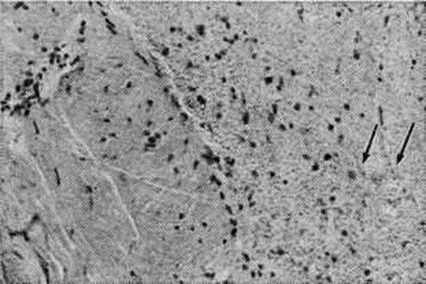

Рис. 2.

Микропрепарат твёрдой мозговой оболочки при геморрагическом пахименингите: пролиферация фибробластов (указано стрелками) в зоне кровоизлияния; окраска гематоксилин-эозином; × 200.